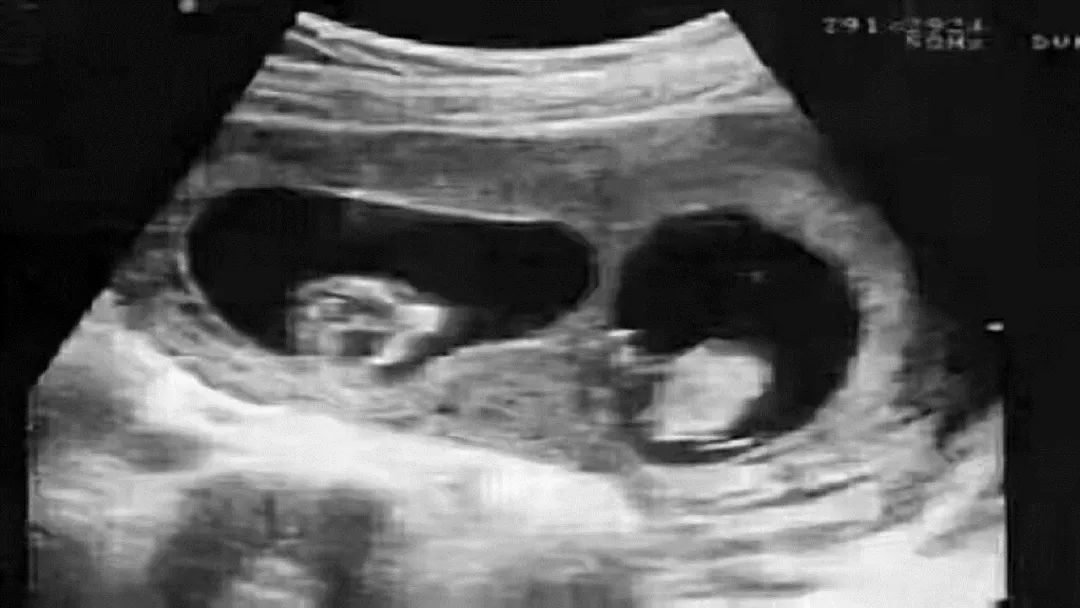

这可能就遇到了鉴定行业中非常罕见的嵌合体案例,也就是说,这位“爸爸”身体内携带有两个人的DNA,可能他在妈妈肚子里的时候,还有一个双胞胎弟弟,但是这个双胞胎弟弟的胚胎没有发育下来,反而和他的胚胎出现了融合,导致这个“爸爸”携带两个人的DNA出生,而且他把弟弟的DNA传给了孩子。

嵌合体其实也称为“奇美拉”现象。奇美拉原本指的是希腊神话中,一种狮头,羊身蛇尾的怪物,可以参考中国的四不像。而嵌合体正是一个人的体内含有多组DNA的现象,也可以通俗的理解为两个受精卵融合成一颗的现象。科学家认为这个发作概率大概在10%-15%。